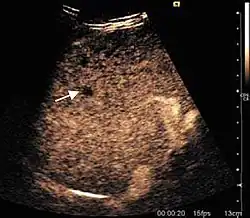

US examination is required to detect liver metastases in patients with oncologic history. In addition, the method can incidentally detect metastases in asymptomatic patients. Early identification (small sizes, small number) is important to establish an optimal course of treatment which can be complex (chemotherapy, radiofrequency ablation, surgical resection) but welcomed. In addition, discrimination of synchronous lesions that have a different nature is also important knowing that up to 25–50% of liver lesions less than 2 cm detected in cancer patients may be benign . US sensitivity for metastases detection varies depending on the examiner's experience and the equipment used and ranges between 40 and 80% . Sensitivity is conditioned by the size and acoustic impedance of the nodules. For a lesion diameter below 10 mm US accuracy is greatly reduced, reaching approx. 20%. Other elements contributing to lower US performance are: excessive obesity, fatty liver disease, hypomobility of the diaphragm, and certain patterns of hyperechoic or isoechoic metastases that can be overlooked or can mimic benign conditions. Conventional US appearance of metastases is uncharacteristic, consisting of circumscribed lesions, with clear, imprecise or "halo" delineation, with homogeneous or heterogeneous echo pattern. They can be single (often liver metastases from colonic neoplasm) or multiple. Echogenity is variable. When increased, they can compress the bile ducts (which may be dilated) and the liver vessels. Liver involvement can be segmental, lobar or generalized. In this situation a pronounced hepatomegaly occurs. Generally, metastases have non-characteristic Doppler vascular pattern, with few exceptions (carcinoid metastases). Cyst-adenocarcinoma metastases due to semifluid content may have a transonic appearance. When increasing, they can result in central necrosis. CEUS examination is a real breakthrough for detection and characterization of liver metastases.

Increased performance is based on identifying specific vascular patterns during the arterial phase and seeing metastases in contrast to normal liver parenchyma during the sinusoidal phase. CEUS increased accuracy is due to the different behavior of normal liver parenchyma (captures CA in Kuppfer cells) against tumor parenchyma (does not contain Kuppfer cells, therefore CEUS appearance is hypoechoic). To this adds the particularities of intratumoral circulation represented by a reduced arterial bed compared to that of the surrounding normal liver and the absence of the portal vessels . In terms of vascularity, metastases can be hypovascular (in gastric, colonic, pancreatic or ovarian adenocarcinomas) with hypoechoic pattern during arterial phase, and similar during portal venous and late phases, respectively hypervascular (neuroendocrine tumors, malignant melanoma, sarcomas, renal, breast or thyroid tumors) with hyperechoic appearance during arterial phase, with washout during the portal venous phase and hypoechoic pattern 30 seconds after injection.